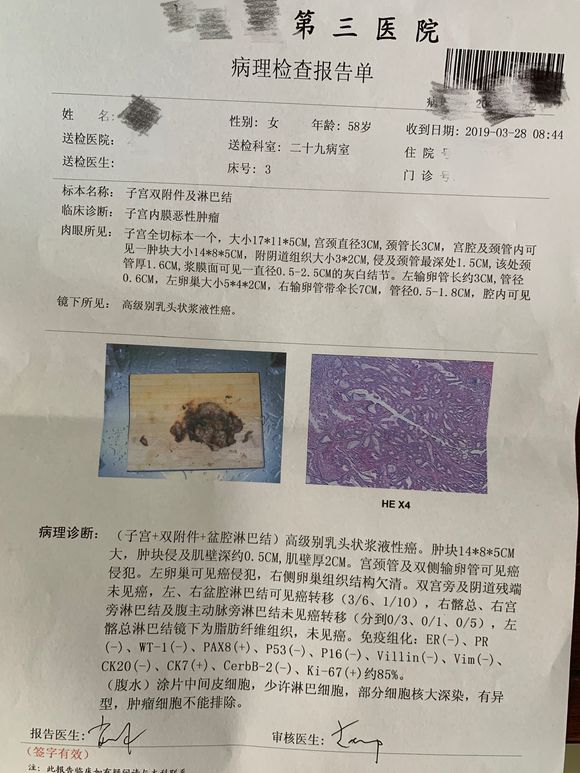

和你的故事 02019-04-09 患者家属我妈妈的病理结果报告,3期c1,大家可以帮忙看看吗,跪求了!我很急,谢谢!想知道是否严重,目前等术后出院后去肿瘤医院...